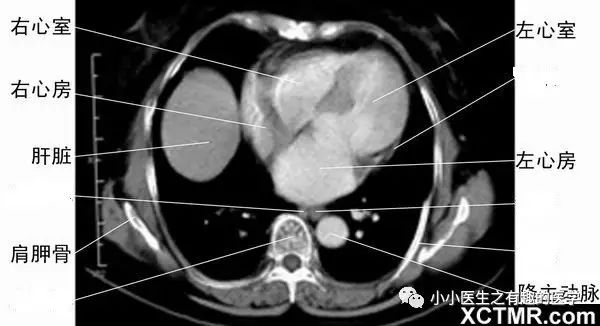

7.要知道左心房、左心室、右心房、右心室,因为这个层面,一般就是中叶、下叶基底段,不再是背段,上叶也几乎不在这里了。

有时,也是这样的。

四个心腔,很简单,在下边的是左心房,左心房和左心室相连。右边也如此,心室都在病人左侧。